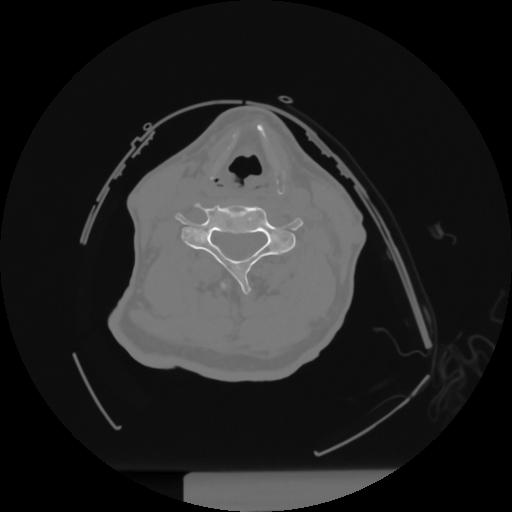

12 P.BLANDAS,,Vol,0.5,P.BLANDAS,,